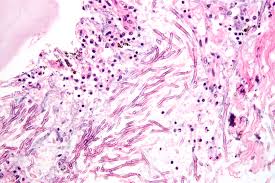

Back in the laboratory, 201 bacterial strains were retrieved from their samples and tested against Aspergillus fumigatus, a fungus that causes invasive aspergillosis in immunocompromised patients.

Of these, 29 showed antifungal activity, but a bacterium called Pseudomonas cichorii showed the greatest potential to inhibit the growth of A fumigatus.

After identifying the most promising bacteria, the scientists used mass spectrometry and molecular networking techniques to determine among all the chemical compounds produced by P cichorii, which one was keeping the fungi at bay.

They also observed the interactions between this bacteria and A fumigatus to identify the bacterial compounds acting in areas where fungal activity was most inhibited.

The main compounds were cyclic lipopeptides that included massetolides and viscosin.

The team then separated viscosin from the other components produced by P cichorii and tested it invitro against A fumigatus and the chytrid fungus. The results confirmed that viscosin displayed significant activity against both.